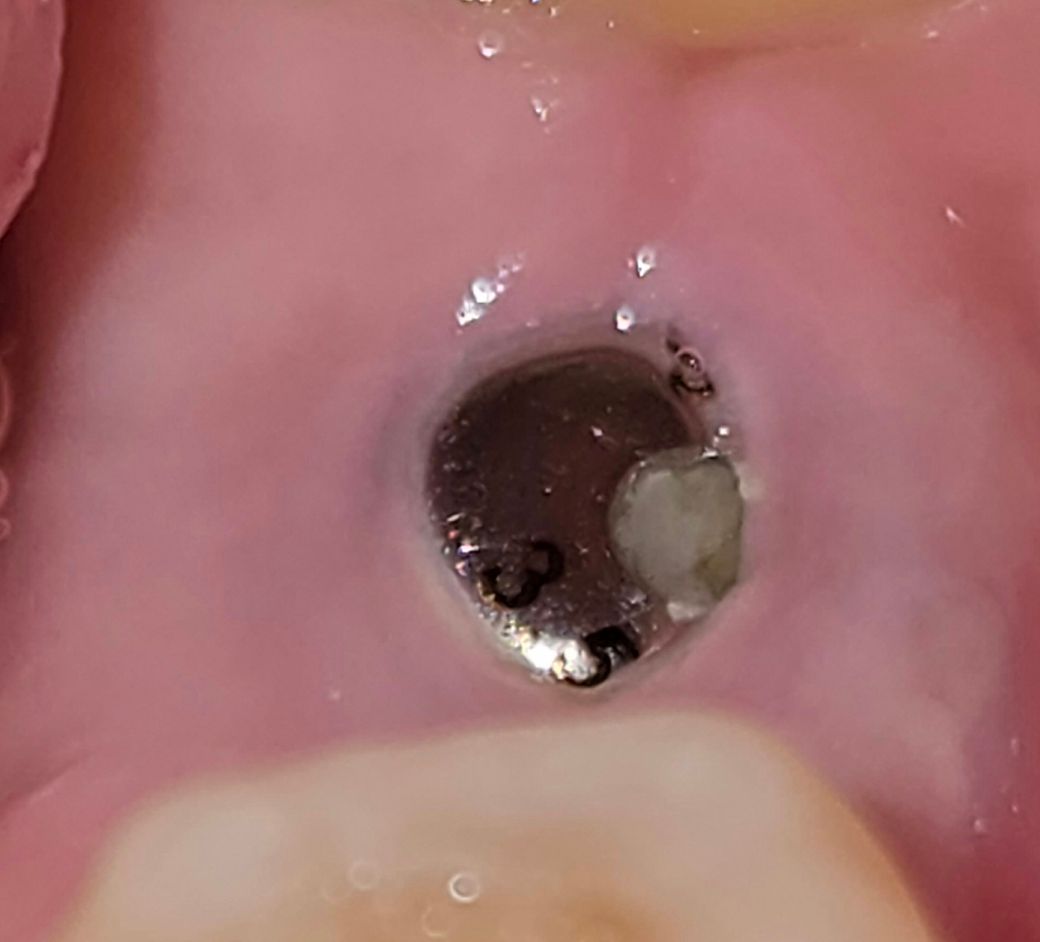

힐링어버트먼트 구멍에 플라그가 쌓여요.

사진처럼 힐링 어버트먼트가 잇몸 속에 있는데요,

가운데 구멍에 자꾸 플라그나 음식물이 쌓이는데,

양치질로 살살 제거 해 봐도 플라그가 남아있습니다.

구멍이 반쯤 잇몸 속에 들어가 있어서 그러는데 이것 때문에 염증이 생길까 걱정입니다. 괜찮을까요?

• 1번 째 사진